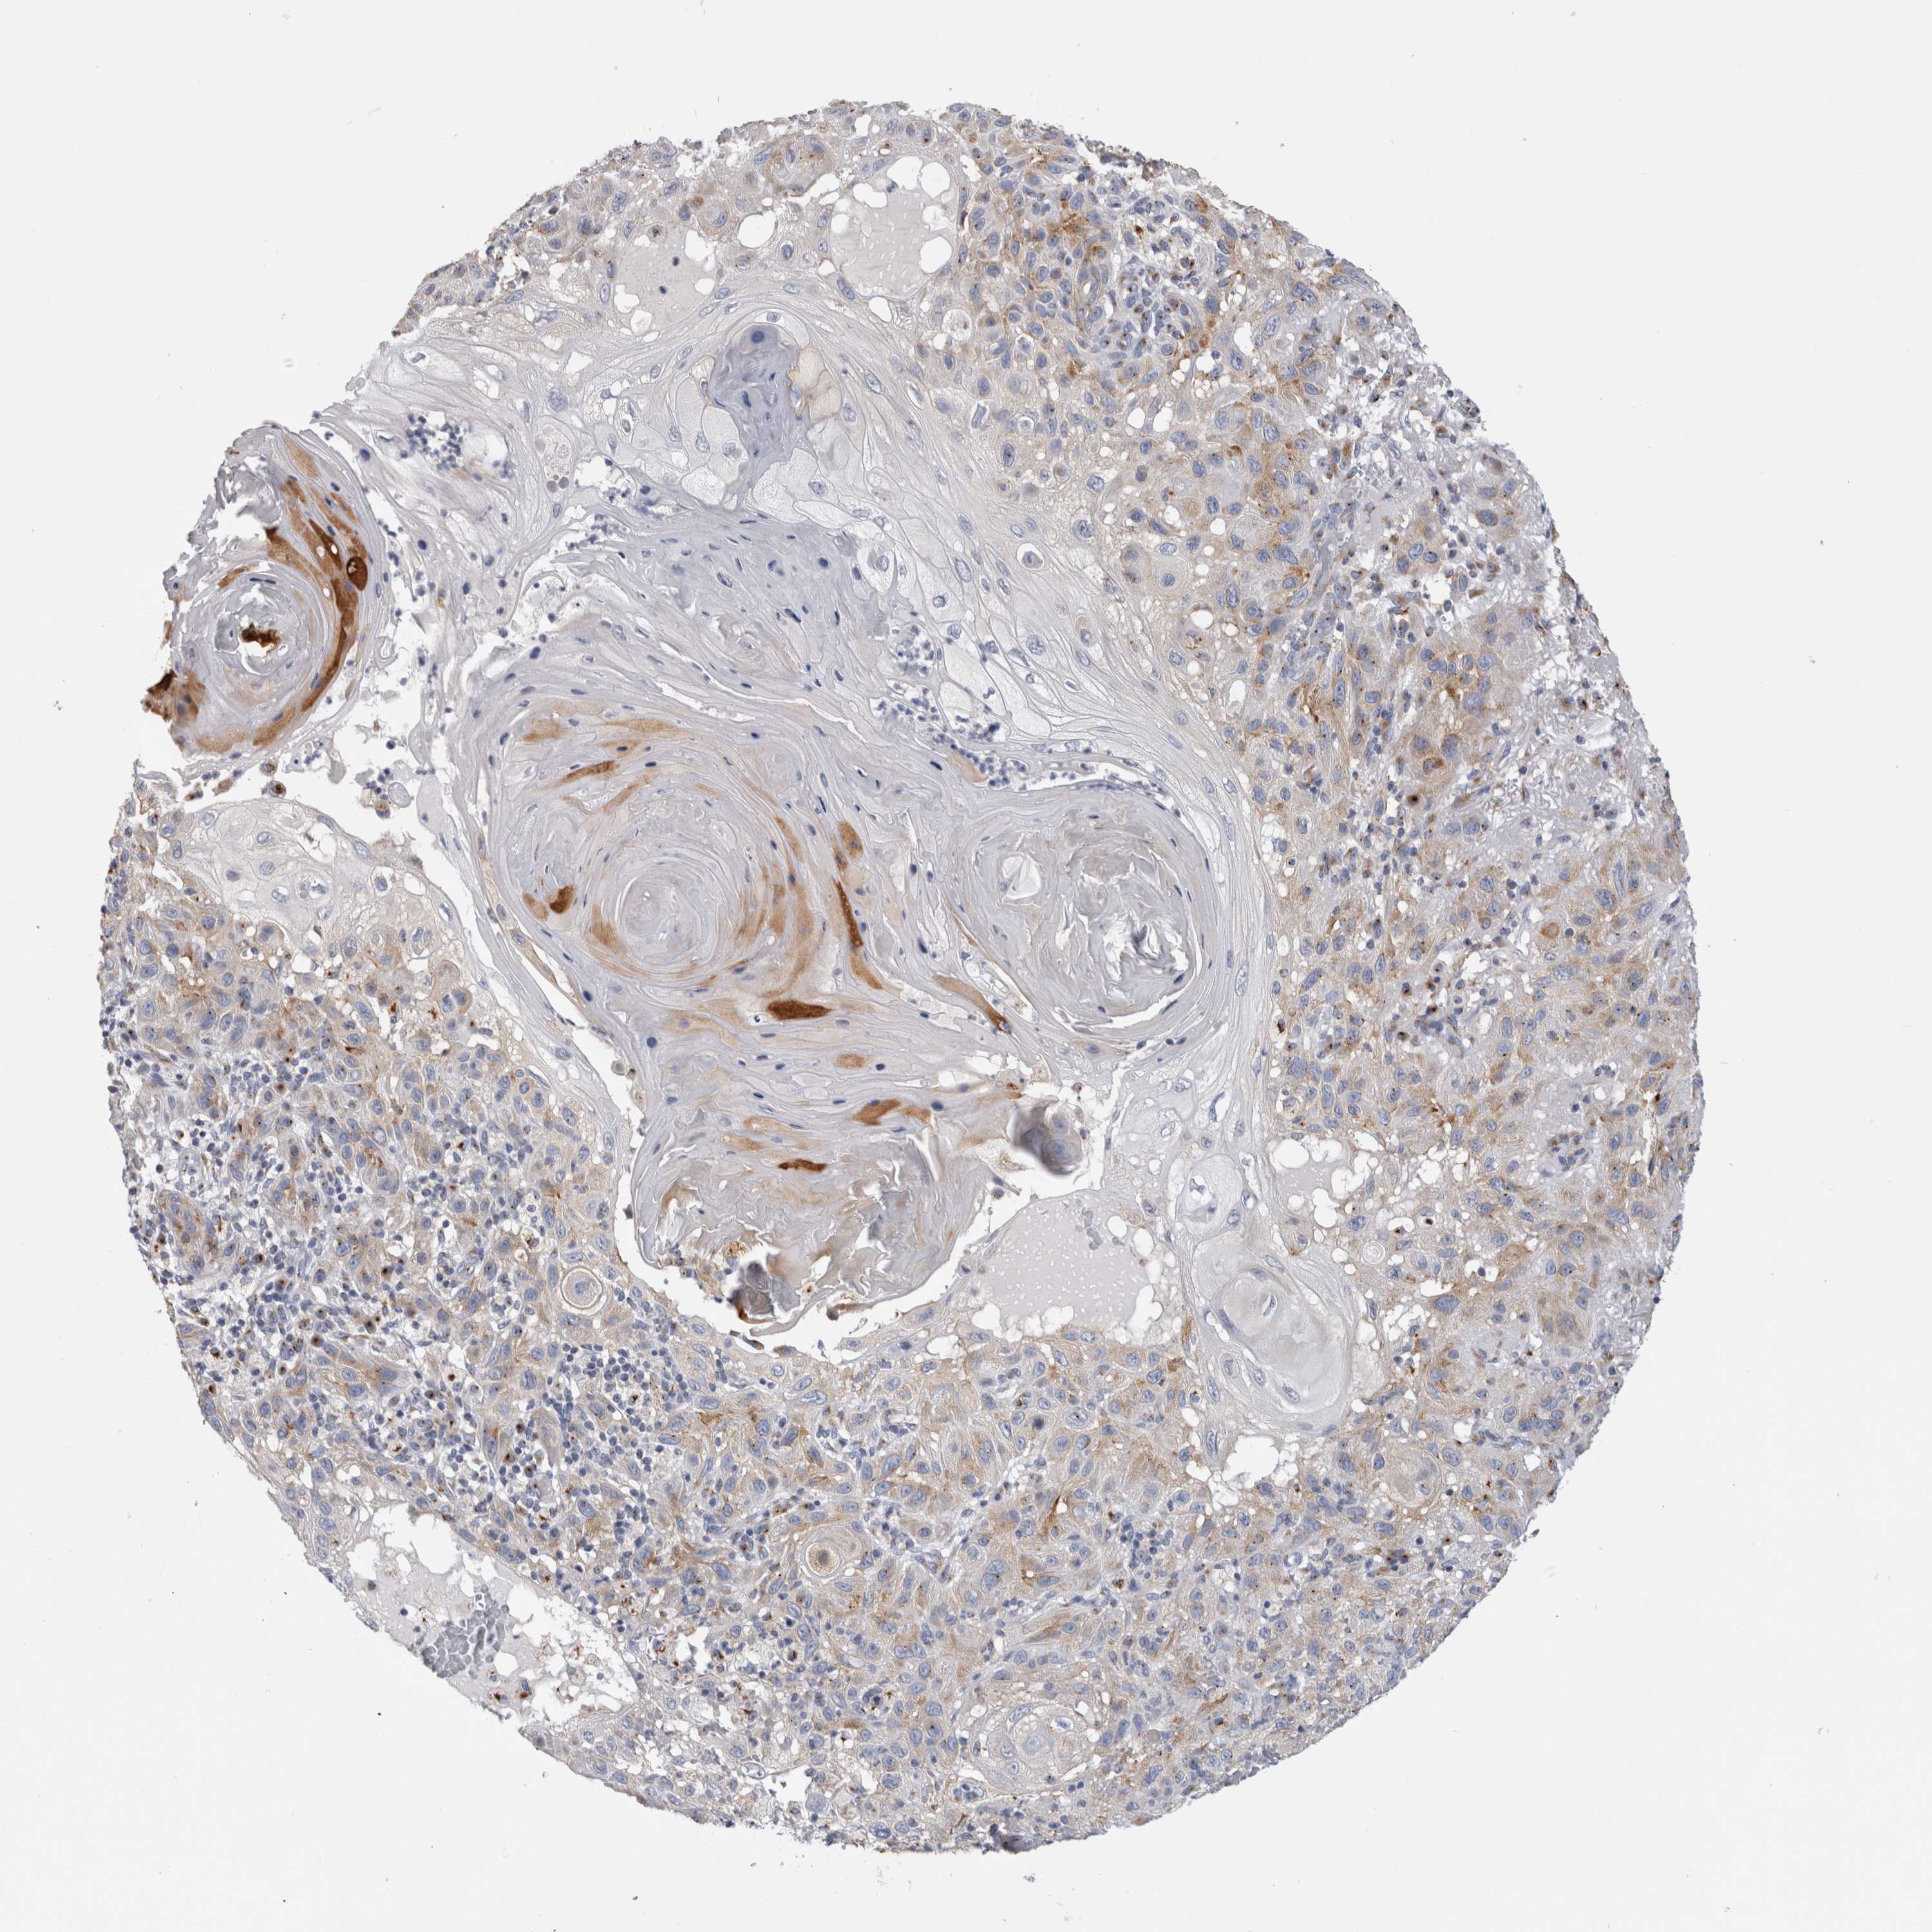

SKIN CANCER - Protein expressioni

A mouse-over function shows sample information and annotation data. Click on an image to view it in a full screen mode. Samples can be filtered based on level of antibody staining by selecting one or several of the following categories: high, medium, low and not detected. The assay and annotation is described here.

Antibody stainingi

Antibody staining in the annotated cell types in the current human tissue is reported as not detected, low, medium, or high, based on conventional immunohistochemistry profiling in selected tissues. This score is based on the combination of the staining intensity and fraction of stained cells.

Each image is clickable and will lead to virtual microscopy that enables deeper exploration of all samples and also displays staining intensity scores, fraction scores and subcellular localization as well as patient and tissue information for each sample.

Antibody CAB012909

Staining

High

Medium

Low

Not detected

Intensity

Strong

Moderate

Weak

Negative

Quantity

>75%

75%-25%

<25%

None

Location

Nuclear

Cytoplasmic/membranous

Cytoplasmic/membranous,nuclear

Squamous cell carcinoma, NOS

Squamous cell carcinoma, metastatic, NOS